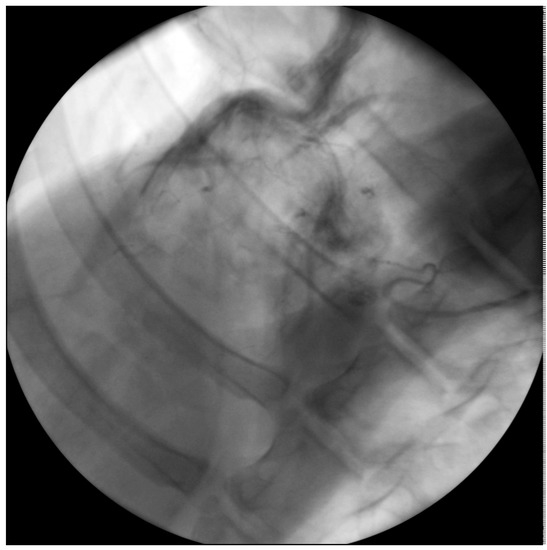

Figure 8. Angiography 3 months after implantation. Retrograde flooding of the contrast agent from the gastric patch artery into the coronary vasculature of the heart.

The contrast agent administered to the left epigastric artery revealed a good openness of the branches supplying the stomach graft in all the examined animals. The stomach segment was excellently supplied with blood both in the 3M and in the 6M group. Besides this, The contrast agent administered to the left epigastric artery flooded into the native coronary arteries (Figure 8). This indicates an in vivo anastomosis of the two different vascular systems.